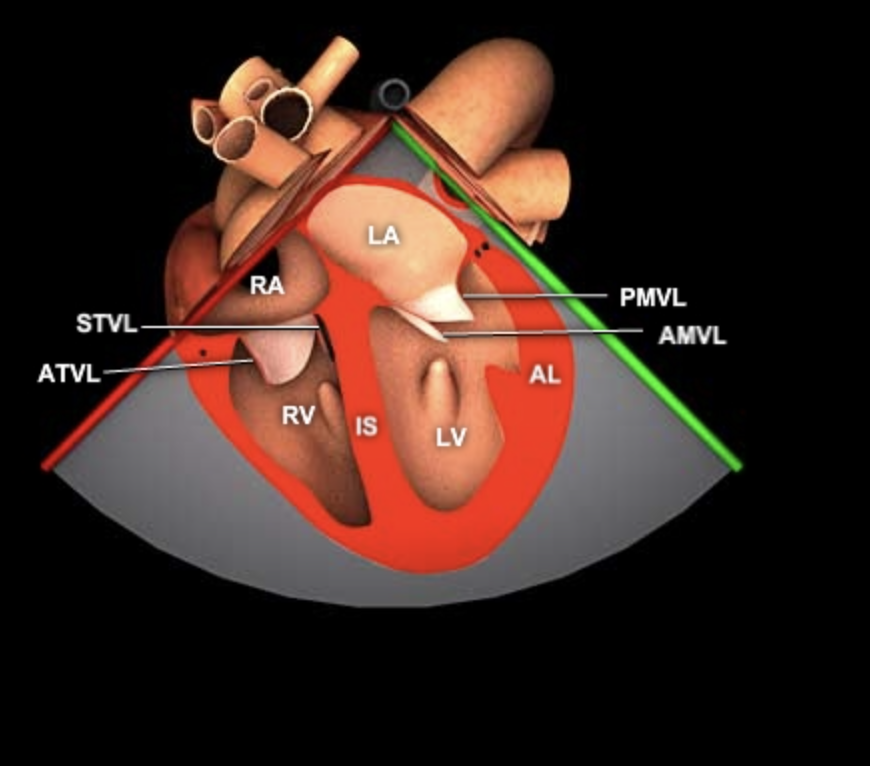

Mid-Esophageal 2-Chamber (ME 2C)

- von ME 4C

- Winkel 90°

- Ziel: MK zentral

- Ziel: RA+RV verschwinden, LAA erscheint

- Zielstrukturen

- LAA

- Coronarsinus (CS)

- MK posteriores+anteriores Segel

- LV Wände (anterior+inferior)

- Danach ME LAX